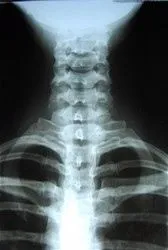

Digital X-Ray Imaging

X-rays are often taken on most patients to give the doctor an inside look at what is going on with the bone structure of the entire spine and surrounding skeletal structure. From this x-ray, the doctor can tell your current spine angles as well as any potential further issues including the potential for additional information such as an MRI.